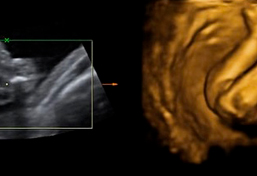

Indice Desarrollo cognitivo y social del bebé de cinco meses Juegos estimulantes para bebés de 5 meses Alimentación del bebé El sueño del bebé con 5 meses Desarrollo cognitivo y social del bebé de cinco meses Su mente se excita si oye que se acerca alguien Ya es capaz de expresar su incomodidad o su inseguridad, e incluso emite muchos sonidos para llamar la atención y levantaEl útero tiene el tamaño de un coco MES 5 El Bebé Su cuerpo se cubre de lanugo y vernix caseosa (fino vello y unto) Tiene pelo, pestañas y cejas Se chupa el dedo Duerme de 18 a horas al día Mide 25 cms y pesa 245 grs La Madre El útero alcanza el nivel del ombligo, teniendo el tamaño de un melón MES 6 El BebéEn los restantes 607 fetos, la confrmación del sexo fetal fue posible en 598 casos (98,5%) La edad gestacional media fue de 124 semanas y el CRL medio fue de 61,2 ± 9,5 mm El sexo fetal fue correctamente asignado por ecografía en el 86,3% de los fetos (516/598)

17 semanas y 5 dias, pesa 250 gramos y mide 23 centimetros, es mas grande de lo que deviera por eso yo pienso que tengo mas tiempoAunque el desarrollo de la vulva o el pene del bebé empieza antes de la semana 6 del embarazo, las hembras y los varones son bastante similares en apariencia hasta la semana 14 del embarazo Para la semana 18, puede que tu médico logre determinar el sexo del bebé si su posición deja los genitales visibles Transcripción El sexo de tu bebé se determina durante la concepción Alrededor de las siete semanas, los órganos sexuales internos de tu bebé, como ovarios, y testículos, se comienzan a formar en el abdomen Los órganos sexuales masculinos y femeninos y sus genitales se ven iguales en esta etapa porque se derivan de las mismas estructuras Alrededor de las